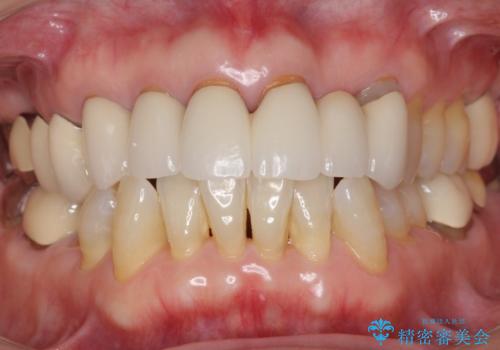

金属を使わないジルコニアセラミッククラウンの自然な仕上がりにご満足頂けました。

単冠の部位は天然歯のようにフロスを通すことができるため、セルフメンテナンスもしやすくなったと患者様に喜んで頂けました。

被せ物の種類:ジルコニアセラミッククラウン スタンダード